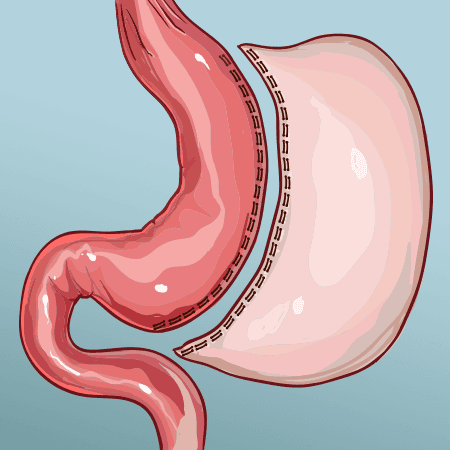

- Gastric Sleeve

- Vertical Sleeve Gastrectomy

| Gastric Sleeve | $3,999 USD | 4 days 3 nights |